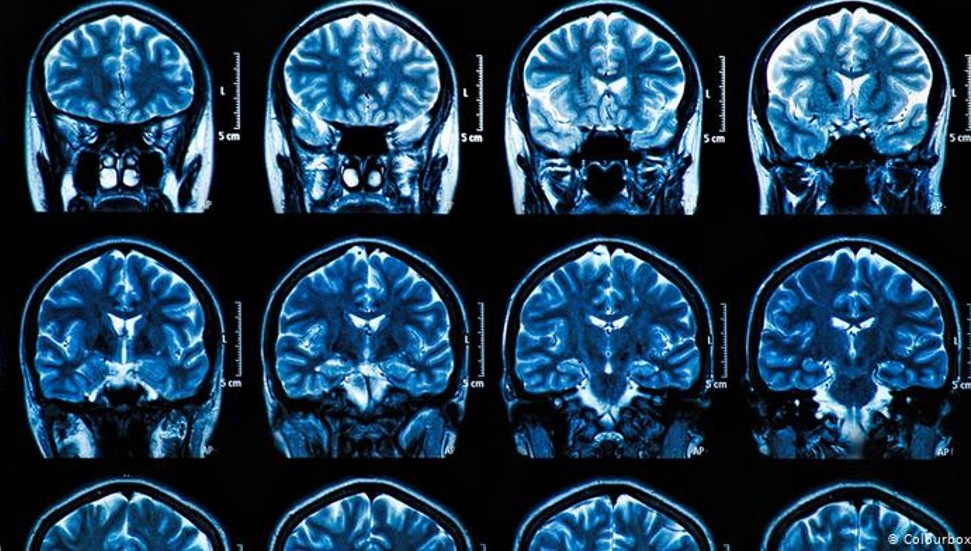

Araştırmacılar, travma ile beyaz cevher hiperintensiteleri arasında bir bağlantı olup olmadığını öğrenmek istediler. Beyaz cevher hiperintensitesi, kan akışındaki bozulmaya neden olup beyinde hasar bırakabiliyor. Beyaz cevher hiperintensiteleri, beyin taramalarında küçük beyaz noktalar olarak ortaya çıkıyor ve bunama, felç ve benzeri rahatsızlıkların erken belirtisi olarak kabul ediliyor. Beyin taramalarında, hastalıkların fiziksel koşulların ortaya çıkmasından on yıllar önce tespit edilebiliyor. Araştırmaya katılan kadınların beyin taramaları, travma yaşayan kadınların, travma yaşamayan kadınlara göre daha fazla beyaz cevher hiperintensitesine sahip olduğunu ortaya koydu. Sonuçta beyaz cevher hiperintensitesi ile cinsel saldırı kaynaklı travma yaşamak arasında bağlantı olduğu ortaya çıktı.